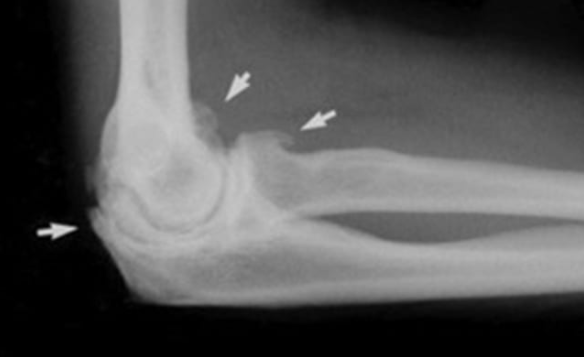

- 영상 진단 검사:Imaging Tests:

- X-ray (X선): 뼈의 상태를 평가하여 골절이나 관절염 같은 문제를 진단할 수 있습니다.